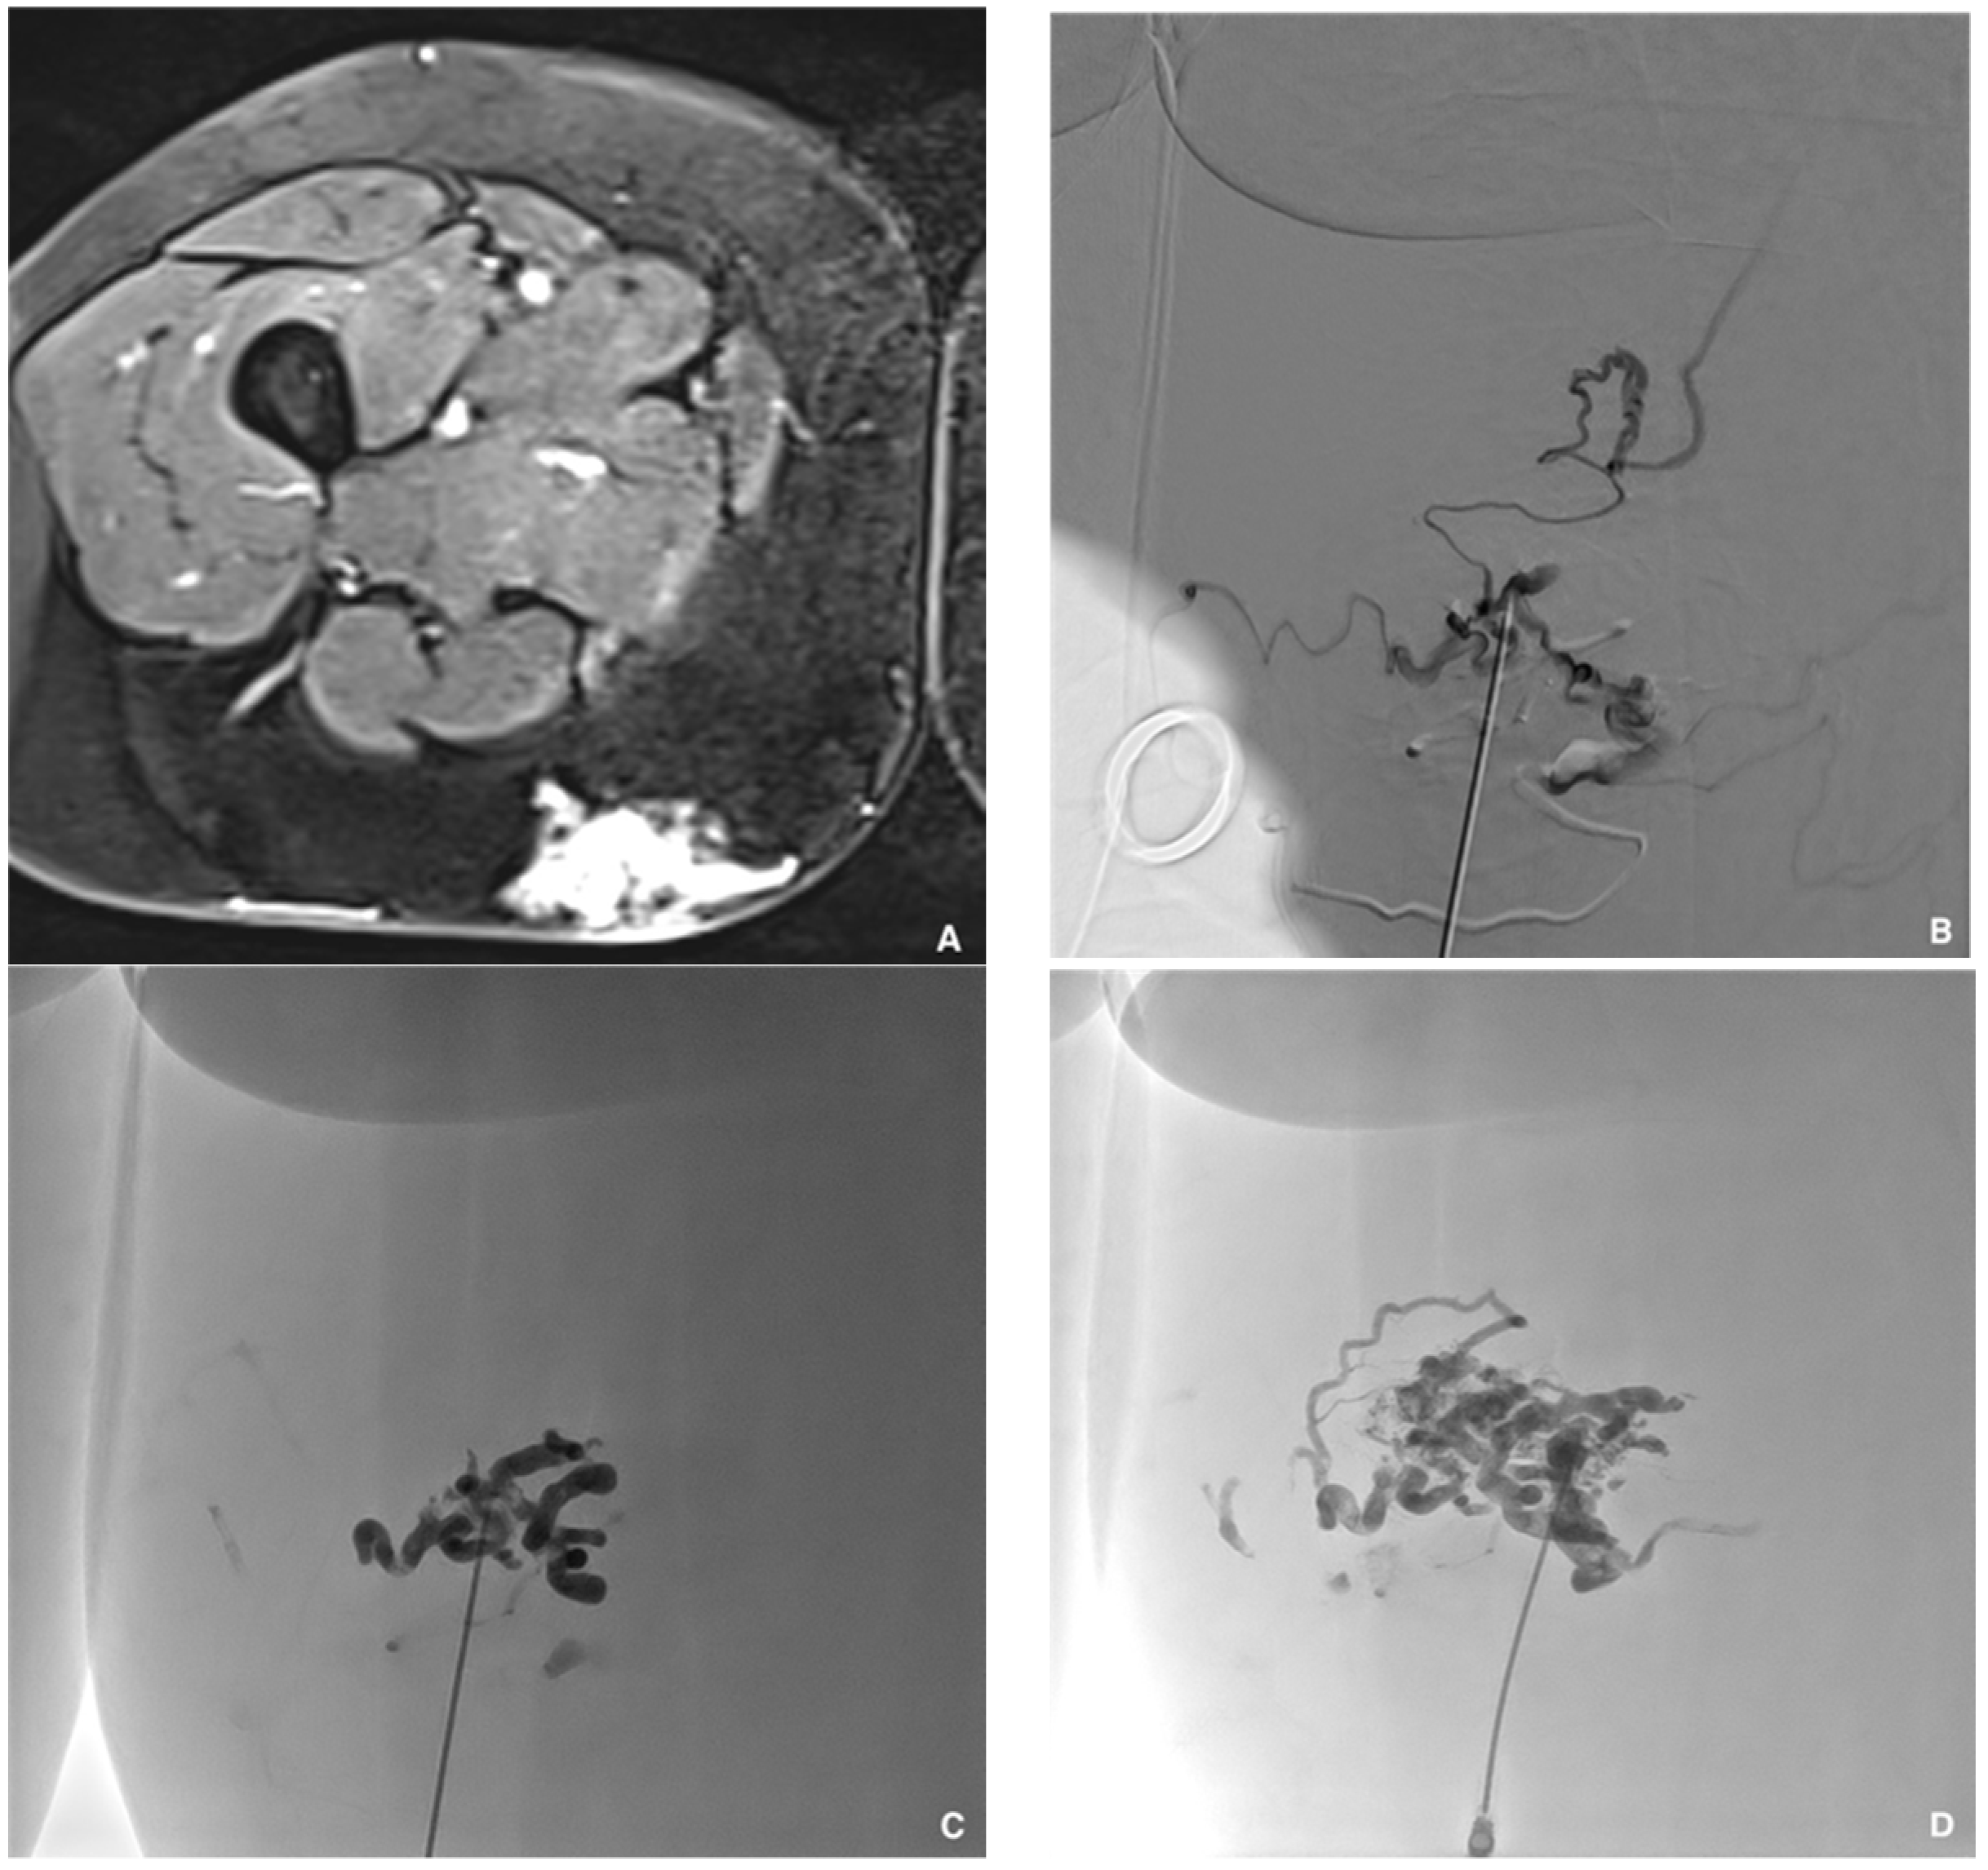

Figure 5. Superficial painful buttock arteriovenous malformation (AVM) in a 61-year-old patient. (A) Axial magnetic resonance imaging shows posterior subcutaneous contrast enhancement at the arterial phase, corresponding to the AVM. (B) Direct puncture of the nidus with a 21-gauge metallic needle and opacification of the nidus. (C) Embolization with a Glubran®2/Lipiodol® mixture of a 1:5 ratio. (D) Final result after complete embolization of the nidus.